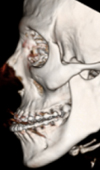

20-Year Follow-Up and Reconstruction of a Patient with Craniofacial Microsomia

A 20-year-old female patient underwent ligation of her external carotid artery due to life threatening haemorrhagic episodes following a biopsy as a n... Read more

10.36959/605/540